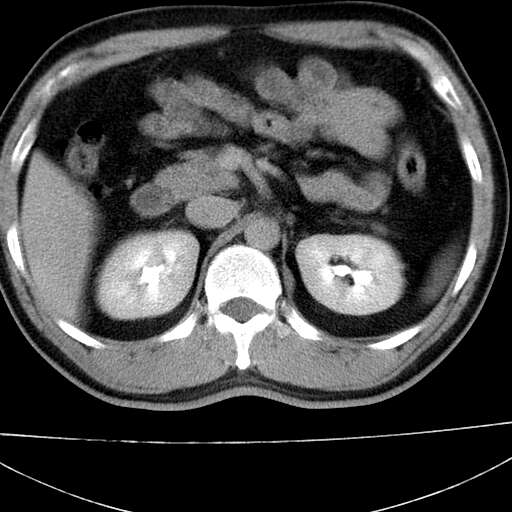

标题: CT21921:腹膜后腔肿物。患者男39Y。体检。增强扫描时间欠准 [打印本页]

左侧膈肌脚外缘见一结节样软组织影,密度较均匀,与胸膜关系稍密切,增强轻度强化;考虑来自胸膜良性病变(胸膜纤维瘤可能)。建议加扫胸部ct检查。

2、左下膈肌脚外缘结节状病变,与胸膜交界面呈锐角,胸膜下脂肪线可见,定位于肺内,考虑支气管囊肿或肺隔离征可能性大。

1)考虑左肺下叶后基底段(或左下胸后壁胸膜)软组织团块,性质待定;建议行进一步检查。2)左肾结石。

左膈肌连续性中断,左侧膈疝可能性大.

左膈肌角后腹膜腔见肿物影,其内见脂肪密度灶及软组织密度灶,强化不明显。病灶大部在后腹膜内。考虑异位嗜铬细胞瘤或脂肪肉瘤、畸胎瘤

左膈肌连续性中断,左侧膈疝可能性大

左下肺隔离症,可见从胸主动脉发出异常血管供应